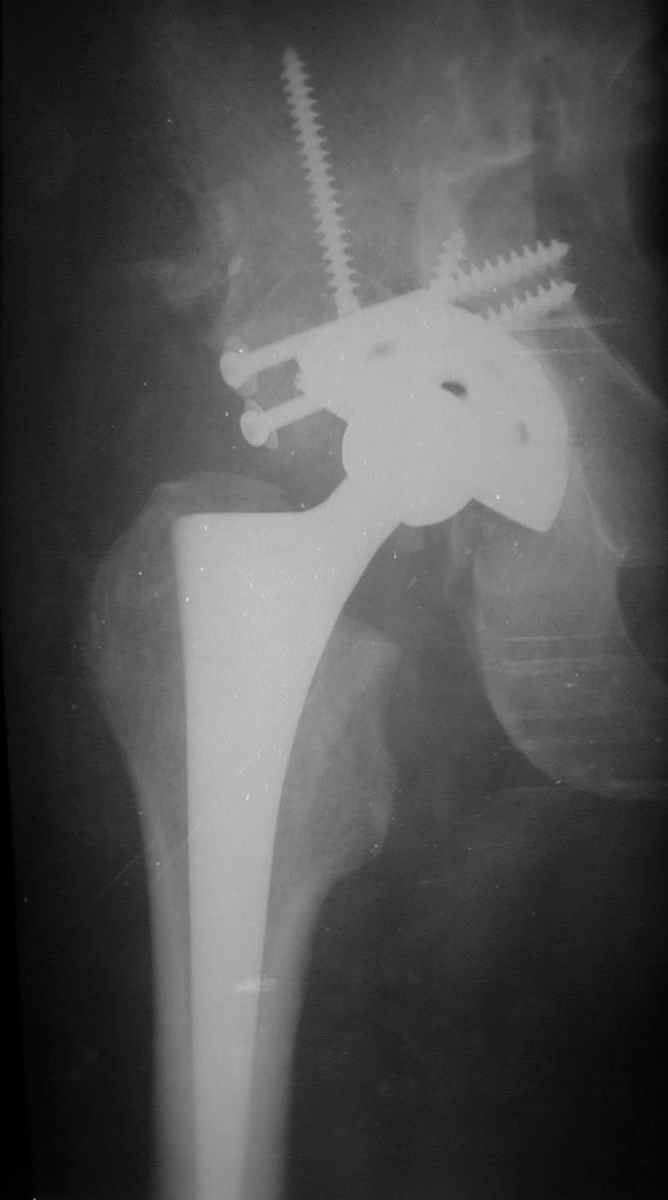

В институте совместно с фирмой Зиммер достаточно регулярно (практически ежемесячно) проводятся 2-х недельные циклы по различным вопросам эндопротезирования. Если есть возможность и желание, мы готовы поделиться с Вами нашим опытом, тем более есть что показать и что обсудить - в настоящее время ежедневно выполняется от 6 до 10 эндопротезирований коленного и тазобедренного сустава. В качестве примеров хочу показать 2 наблюдения, через 1 год и 5 лет после операции

1 год

5 лет